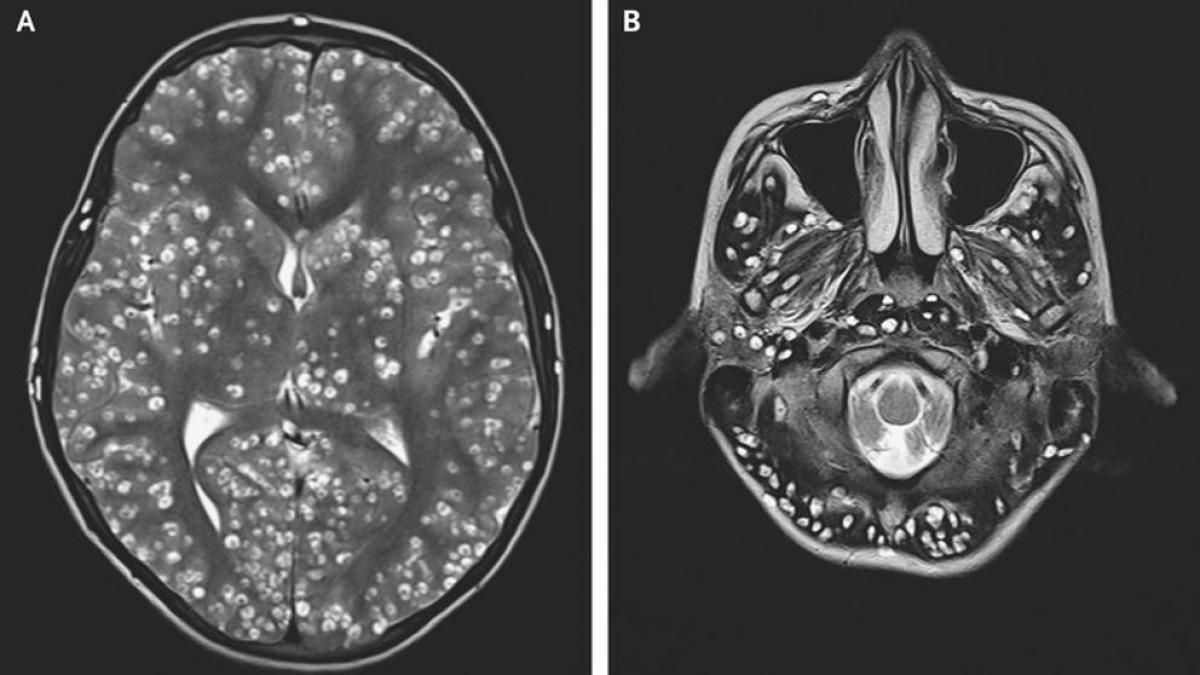

Al realizarle tomografías, los médicos encontraron la presencia de numerosos quistes en el cerebro que, según luego comprobaron con estudios posteriores, en realidad eran larvas de tenia que se habían instalado en su cerebro y que eran las causantes de una infección conocida como neurocisticercosis.

Según los Centros para el Control y la Prevención de Enfermedades (CDC, por sus siglas en inglés), las larvas de tenia “entran en tejidos como los músculos y el cerebro y forman quistes. Cuando se encuentran quistes en el cerebro, la afección se llama neurocisticercosis”.